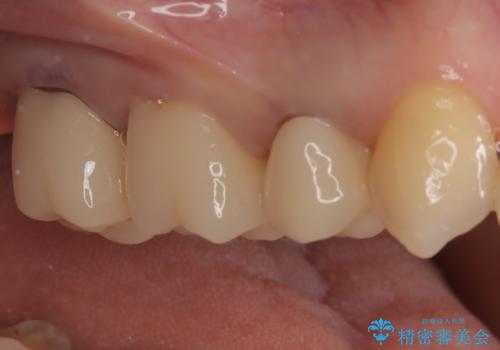

【オールセラミッククラウン】メタルフリー治療

- 古い被せ物をやり変えたいことを主訴に来院されました。

根管治療も行い、きれいな被せ物になり患者さんも喜んでいました。

3本まとめて治療をすることで来院回数を減らし、患者さんの負担を減らすことができ喜んでいただけました。